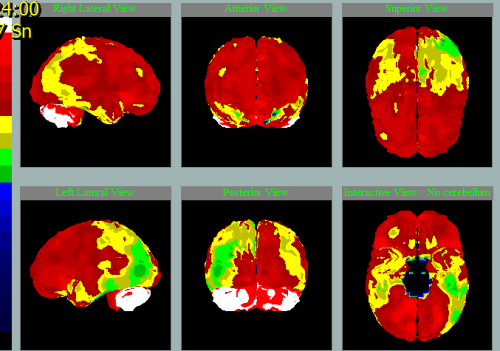

Různé nemoci na SPECT mozku s charakteristickými vzorci hypoperfúze

Frontotemporální lobární degenerace

Pedevším temporální hypoperfúze vlevo.

Především frontální hypoperfúze oboustranně.

Především frontotemporální hypoperfúze vlevo.

Nemoc s Lewyho tělísky